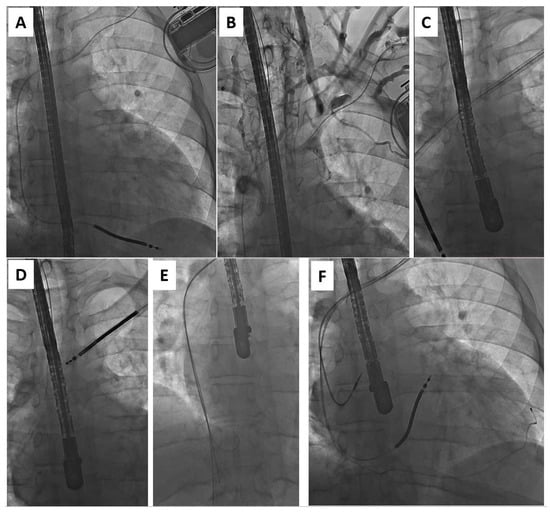

Antibiotic prophylaxis in all patients consisted of a first-generation cephalosporin administered as a bolus an hour before TLE. In most procedures, standard stylets were used to stiffen the leads. Locking stylets (Liberator Locking Stylet, Cook Medical Inc., Bloomington, IN, USA) were used only for the extraction of the oldest leads when the estimated risk of lead break was high. Simple traction or traction on a locking stylet with insulation-bound suture was very rarely applied as our intention was to preserve or restore venous access for the implantation of a new lead(s) (Figure 1). Lead extraction was usually performed using non-powered mechanical telescoping polypropylene sheaths (Byrd Dilator Sheaths, Cook Medical Inc., Bloomington, IN, USA) of all diameters and lengths, and various stylets. When the polypropylene telescoping sheaths appeared ineffective, powered mechanical sheath systems (Evolution Mechanical Dilator Sheath, Cook Medical Inc., Bloomington, IN, USA; TightRail Rotating Dilator Sheath, Spectranetics, Colorado Springs, CO, USA) were used. A combination of approaches, using two or more different (jugular, subclavian, or femoral) access sites, was selected when conventional methods were insufficient. Laser and electrosurgical dissection sheaths were not used.

Figure 1.

Upgrade from ICD-V (A) to CRT-D in the patient undergoing TLE for lead-related venous obstruction (B). Moving the introducer sheath over the lead to the heart facilitates not only the removal of the lead (C) but also reestablishing access for the implantation of three new leads (D).

Figure 3.

Upgrade from ICD-V (A) to CRT-D in the patient with lead-related venous obstruction (B). Moving the preparation sheath over the lead to the heart allows not only for lead removal (C,D) but also reestablishing venous access (E) for the implantation of three new leads (F).